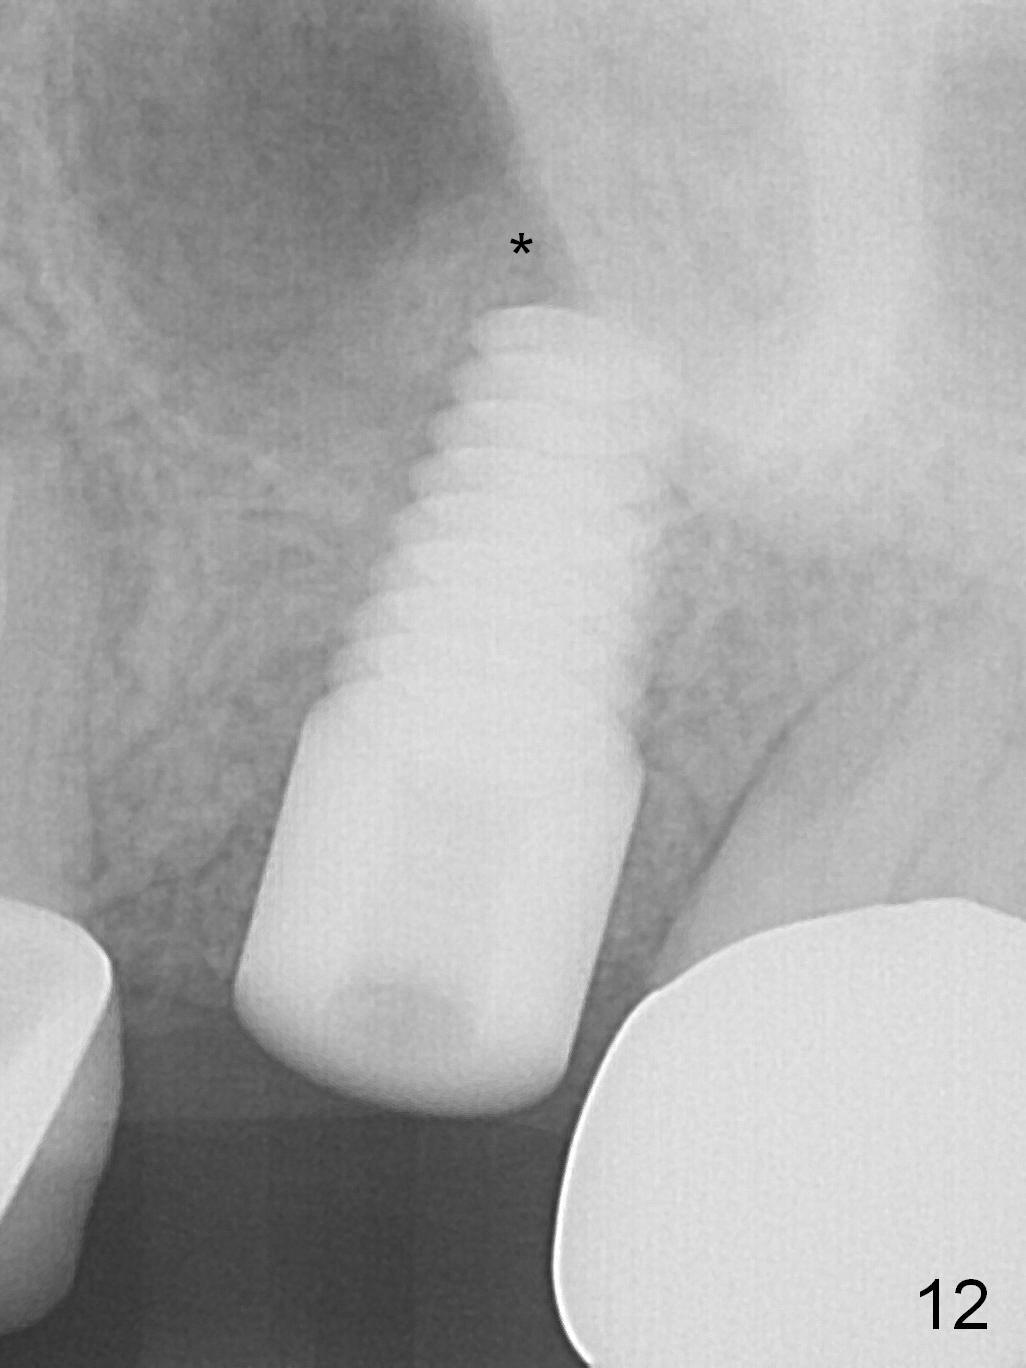

The patient is doing well 9 days postop.  The immediate provisional is loose and over-sized.  It is removed for trimming and reline; the socket and bone graft (Fig.8 *) are healing.  It appears that an angled abutment is required next time of provisional revision.  When an angled abutment is being placed 23 days postop (Fig.9), it appears to wiggle the implant due to its long leverage.  Instead a healing abutment is placed.  The implant is unstable 4.5 months postop with seemingly excessive bone-implant gap (Fig.10 <).  The 5.5x9 mm implant is removed.  A 5x17 mm tap is used to change the trajectory and sinus lift, followed by 6x17 one (Fig.11).  Finally a 6x14 mm tissue-level implant is placed with insertion torque > 50 Ncm (Fig.12; vs. <20 Ncm (Fig.7,10)) and improved trajectory.  An immediate provisional is fabricated to prevent the mesial drifting of the tooth #15 (Fig.13 P (*: occlusal clearance)).  By using the taps and placing the longer implant, the sinus lift is more obvious (compare Fig.10 and 12 (*)).  Sinus lift remains evident 3.5 months postop (Fig.14) with apparently osteointegration (Fig.15).